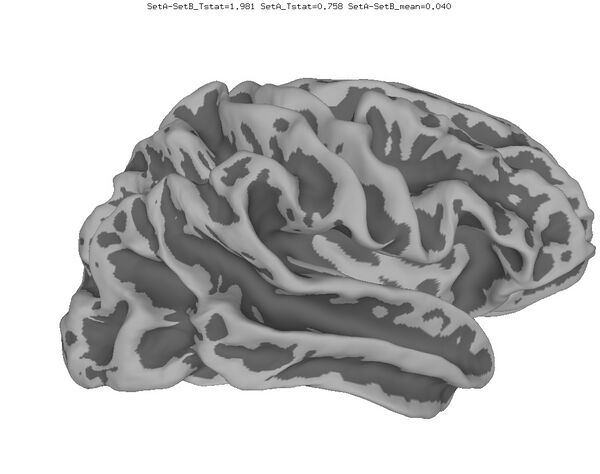

Anatomical Data

New

Functional data of the Mouth vs. Eye contrast mapped to the average surface. It is hard to quantify the difference, but one way is to compare the maximum statistical values; with better intersubject alignment, these would presumably increase.

1. NEW: Max t-value for Mouth: 9.3 Eye:10.1 Eye vs Mouth: 5.6

2. OLD: Max t-value for Mouth: 7.9 Eye:8.8 Eye vs Mouth: 5.8

data from Zhu LL, Beauchamp MS. Mouth and Voice: A Relationship between Visual and Auditory Preference in the Human Superior Temporal Sulcus. Journal of Neuroscience 8 March 2017, 37 (10) 2697-2708; DOI: https://doi.org/10.1523/JNEUROSCI.2914-16.2017. Click here to download the PDF. Surface averages were not used in this paper so the bug did not affect the published results.

Old